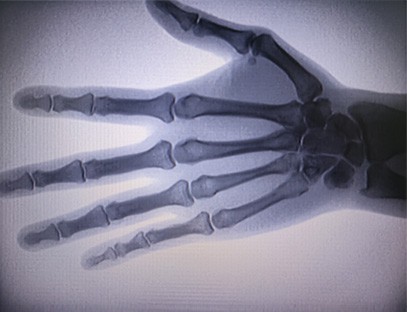

Una máquina de rayos X portátiles un instrumento portátil de baja dosis de radiación, muy seguro, que puede obtener imágenes de alta calidad al tiempo que reduce la exposición a la radiación. Compensa las deficiencias de los grandes equipos hospitalarios y se puede mover y transportar en cualquier momento. Especialmente adecuado para unidades e individuos con presupuesto insuficiente y bajos requisitos de imágenes. Nuestra máquina de rayos X de nueva generación está equipada con una pantalla grande de alta definición de 10 pulgadas, que tiene un rango de ángulo de visión más amplio y puede ver completamente a través de toda la palma, incluidas fracturas, dislocaciones, artritis y tumores óseos. Se puede conectar a una impresora de películas para imprimir películas ortopédicas y también se puede utilizar para producción y pruebas industriales. No necesita un cuarto oscuro, perspectiva directa, observación en tiempo real. Esta máquina tiene un sistema de imágenes de alta resolución que puede capturar imágenes de cualquier estructura ósea con mucha claridad. Proporcionar los mejores equipos y soluciones de prueba de rayos X para fabricantes de productos médicos, de mascotas, industriales, electrónicos, departamentos de inspección y mantenimiento y laboratorios de investigación.

Especialización:Diseñado para las necesidades de las clínicas ortopédicas, especialmente adecuado paraImágenes de rayos Xde extremidades como manos, muñecas, codos, hombros, rodillas, tobillos, etc.

Imágenes claras:Se utiliza tecnología avanzada de imágenes digitales para proporcionar imágenes de rayos X de alta calidad, lo que ayuda a los médicos a diagnosticar la afección con precisión.